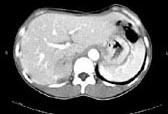

问题 女,35岁,上腹部隐痛不适伴消瘦1月,胃镜提示胃癌,CT扫描如图所示:右侧肾上腺区可见一占位性病灶,应诊断为 ( )

选项 A、右肾上腺嗜铬细胞瘤 B、右肾上腺错构瘤 C、右肾上腺腺癌 D、右肾上腺转移瘤 E、右肾上腺腺瘤

答案 D